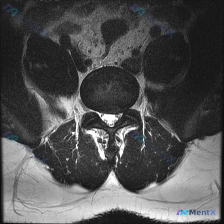

今天整理了一份只有单张腰椎MRI T2加权轴位片的椎间盘病变分析案例,跟大家分享一下读片和临床分析的思路。

本次仅提供单张腰椎MRI T2加权轴位图像,具体读片发现如下:

- 节段定位:根据椎体、椎弓根和关节突形态判断,该切面位于腰椎,最可能为L4/5或L5/S1水平

- 椎间盘表现:髓核T2信号较正常降低,信号不均匀,提示存在椎间盘脱水退变;但纤维环后缘平整,没有明显局限性突出或脱出,硬膜囊前缘形态良好,未见受压变形

- 椎管与侧隐窝:椎管形态正常,无明显骨性狭窄,脑脊液间隙保留良好;双侧侧隐窝通畅,未见上关节突内聚或黄韧带肥厚导致的狭窄,黄韧带厚度在正常范围

- 骨性结构与关节:椎体边缘完整,无明显骨赘或压缩畸形;双侧关节突关节面光滑,间隙正常,无明显增生硬化,也没有滑膜囊肿或积液

- 神经与软组织:硬膜囊内马尾神经根分布正常,无拥挤移位受压;椎旁肌肉信号均匀,未见异常信号或肿块,排除明显感染、肿瘤性病变迹象